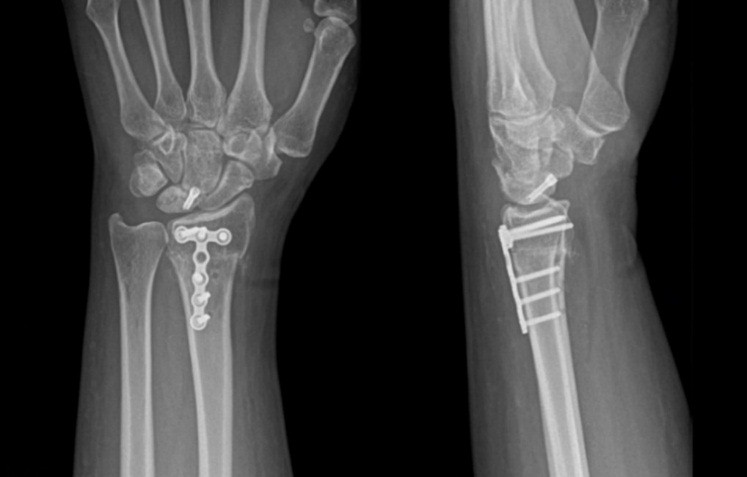

The mean follow-up duration was 24 months (Patient A: 36 months and Patient B: 12 months). Bone consolidation of the radial osteotomy was achieved on average 3 months postoperatively for both patients, while consolidation of the lunate fracture occurred at 6 months for Patient A (Fig. 9) and at 7 months for Patient B (Fig. 10). Lunate fracture union and radial osteotomy union were assessed with CT.

Figure 9: Patient A – X-ray and computed tomography scan: radius/ lunate consolidation.

Figure 10: Patient B X-ray and computed tomography scan: radius/ lunate consolidation.

CT was chosen because it is widely regarded as more reliable than radiographs for assessing carpal bone union and arthrodesis/osteotomy healing, and is appropriate when the clinical course is favorable. Routine post-operative perfusion studies were not pursued because the clinical evolution was satisfactory, and structural union had been demonstrated on CT.